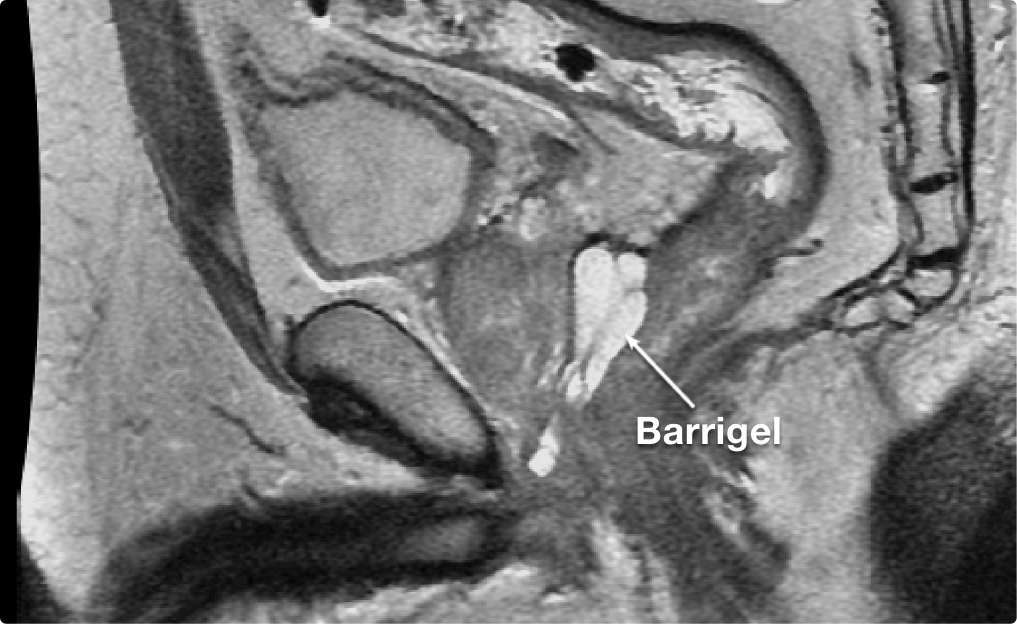

STABILITY MATTERS

STABILITY

MATTERS